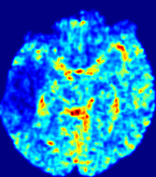

4.3.1 Advection Imaging via Advection-Diffusion

Slice #1Slice #2Slice #3Slice #4Slice #5Slice #6𝐕gt𝟐subscriptnormsuperscript𝐕gt2\|\bf{V}^{\text{gt}}\|_{2}Refer to captionRefer to captionRefer to captionRefer to captionRefer to captionRefer to caption𝐕est𝟐subscriptnormsuperscript𝐕est2\|\bf{V}^{\text{est}}\|_{2}Refer to captionRefer to captionRefer to captionRefer to captionRefer to captionRefer to captionRefer to caption1.51.51.51.21.21.20.90.90.90.60.60.60.30.30.30.00.00.0(mm/s)𝑚𝑚𝑠(mm/s)Destsuperscript𝐷estD^{\text{est}}Refer to captionRefer to captionRefer to captionRefer to captionRefer to captionRefer to captionRefer to caption0.0150.0150.0150.0120.0120.0120.0090.0090.0090.0060.0060.0060.0030.0030.0030.0000.0000.000(mm2/s)𝑚superscript𝑚2𝑠(mm^{2}/s)

Figure 14: PIANO identifiability testing: advection imaging via advection-diffusion. Top row shows 𝐕gt2subscriptnormsuperscript𝐕gt2\|{\bf{V}}^{\text{gt}}\|_{2} used for simulating ground truth pure advection. Rows below show the estimated 𝐕est2subscriptnormsuperscript𝐕est2\|{\bf{V}}^{\text{est}}\|_{2} and Destsuperscript𝐷estD^{\text{est}} on corresponding slices. Note that the plotted value scale for Destsuperscript𝐷estD^{\text{est}} is 0.01 of that for 𝐕gt2subscriptnormsuperscript𝐕gt2\|{\bf{V}}^{\text{gt}}\|_{2} and 𝐕est2subscriptnormsuperscript𝐕est2\|{\bf{V}}^{\text{est}}\|_{2}.

We use the same ‘Advection Imaging’ simulation of Sec. 4.2.1 as the concentration dataset for PIANO. However, instead of modeling pure advection (Eq. 15), we let PIANO estimate both velocity 𝐕estsuperscript𝐕est{\bf{V}}^{\text{est}} and diffusivity Destsuperscript𝐷estD^{\text{est}} via the advection-diffusion PDE (Eq. 2) underlying the proposed PIANO model. Fig. 14 shows the estimated 𝐕est2,subscriptnormsuperscript𝐕est2\|{\bf{V}}^{\text{est}}\|_{2}, and Destsuperscript𝐷estD^{\text{est}} fields for one patient. Although PIANO has the freedom to estimate both a velocity and a diffusivity field from pure advection, PIANO differentiates well between advection and diffusion: the estimated 𝐕est2subscriptnormsuperscript𝐕est2\|{\bf{V}}^{\text{est}}\|_{2} successfully reproduces the ground truth 𝐕gt2subscriptnormsuperscript𝐕gt2\|{\bf{V}}^{\text{gt}}\|_{2} governing the simulated advection process, just as it already did in the ‘Advection Imaging via Advection’ test (Fig. 12). More importantly, the estimated diffusivity Destsuperscript𝐷estD^{\text{est}} is orders of magnitudes smaller than 𝐕est2subscriptnormsuperscript𝐕est2\|{\bf{V}}^{\text{est}}\|_{2}, indicating the estimated diffusion is negligible compared to the estimated advection, which is highly consistent with the underlying pure advection of the simulated data.